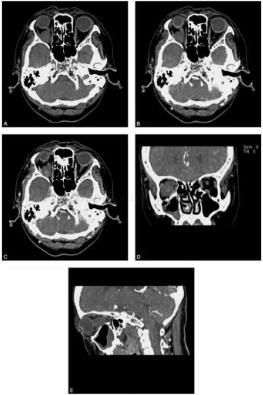

女性患者,62岁。2年前无明显诱因自觉双眼痛、头痛,无畏光流泪,无恶心呕吐,无视物不清。查体可见右侧眼球突出(图1、图2)。

图1 双眶CT平扫、增强扫描及三维重组:图A、图B、图C为横断面平扫、增强早期及延迟期图像,图D、图E分别为冠状面和矢状面图像。右眶内球后可见类圆形软组织密度结节,边缘光滑,界限清楚,周围脂肪间隙清晰,内部密度稍不均匀,与视神经关系密切,增强早期可见病变中心明显强化,延迟扫描强化程度趋于均匀;结合三维重建可见病变位于肌锥内、视神经外下方,局部可见视神经弧形移位